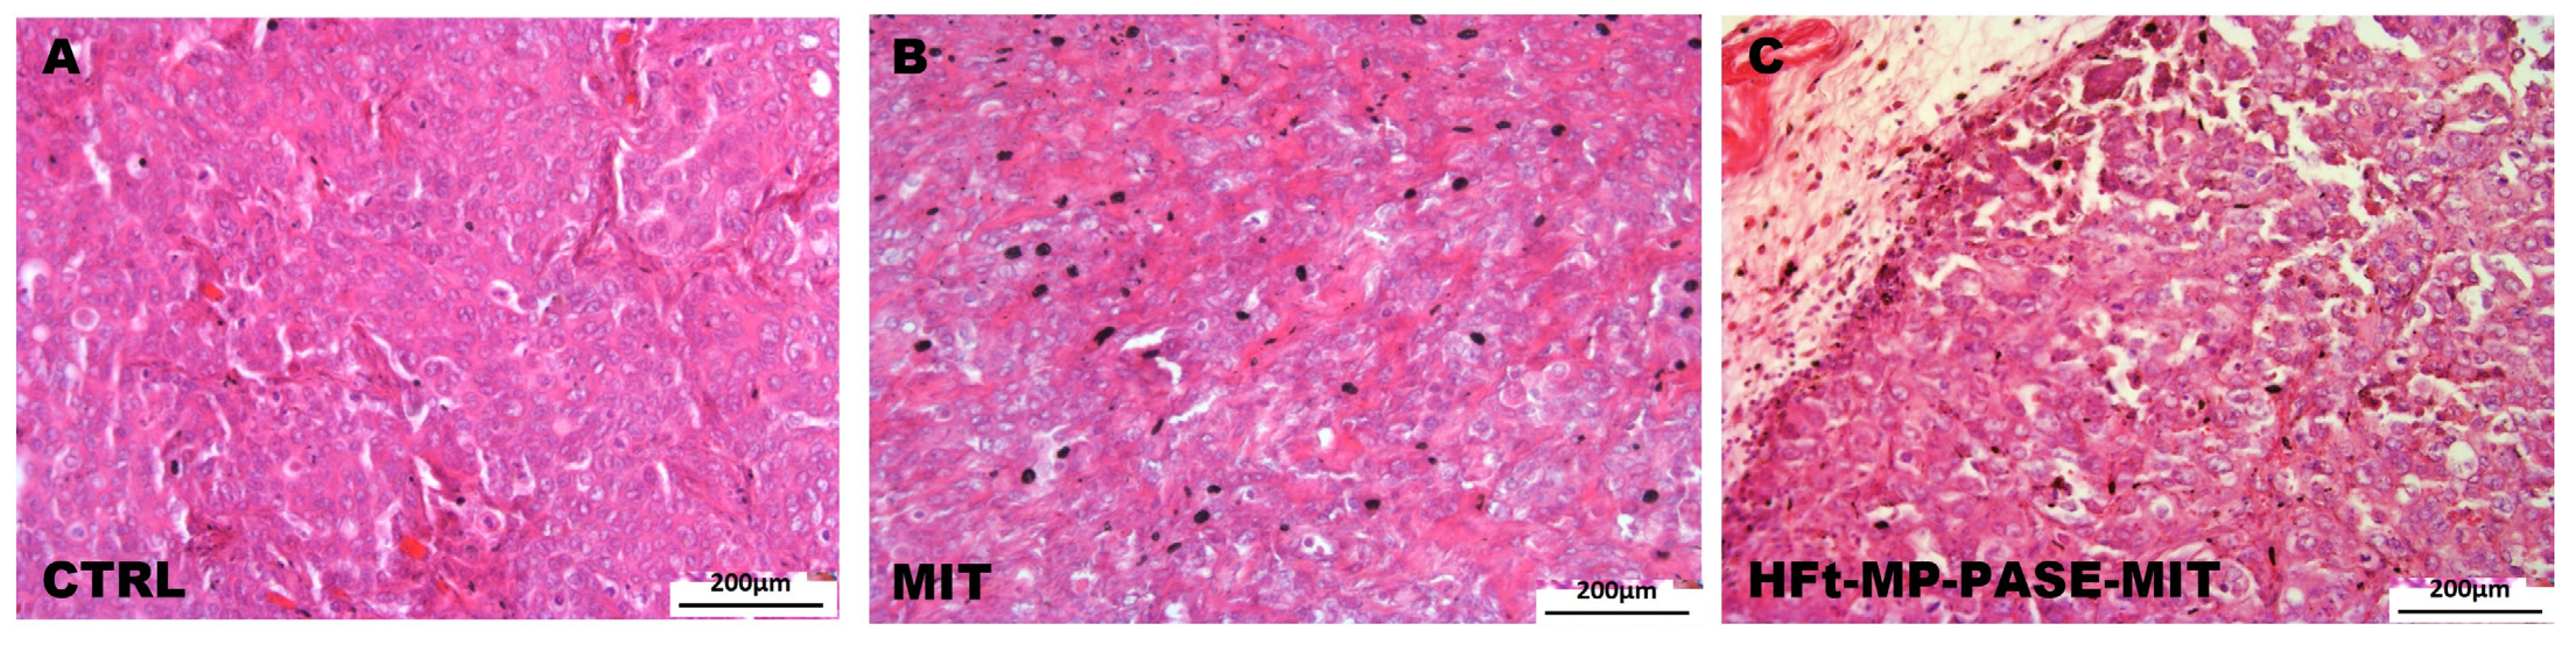

3.6. Histological Evaluation of Primary Tumor Mass